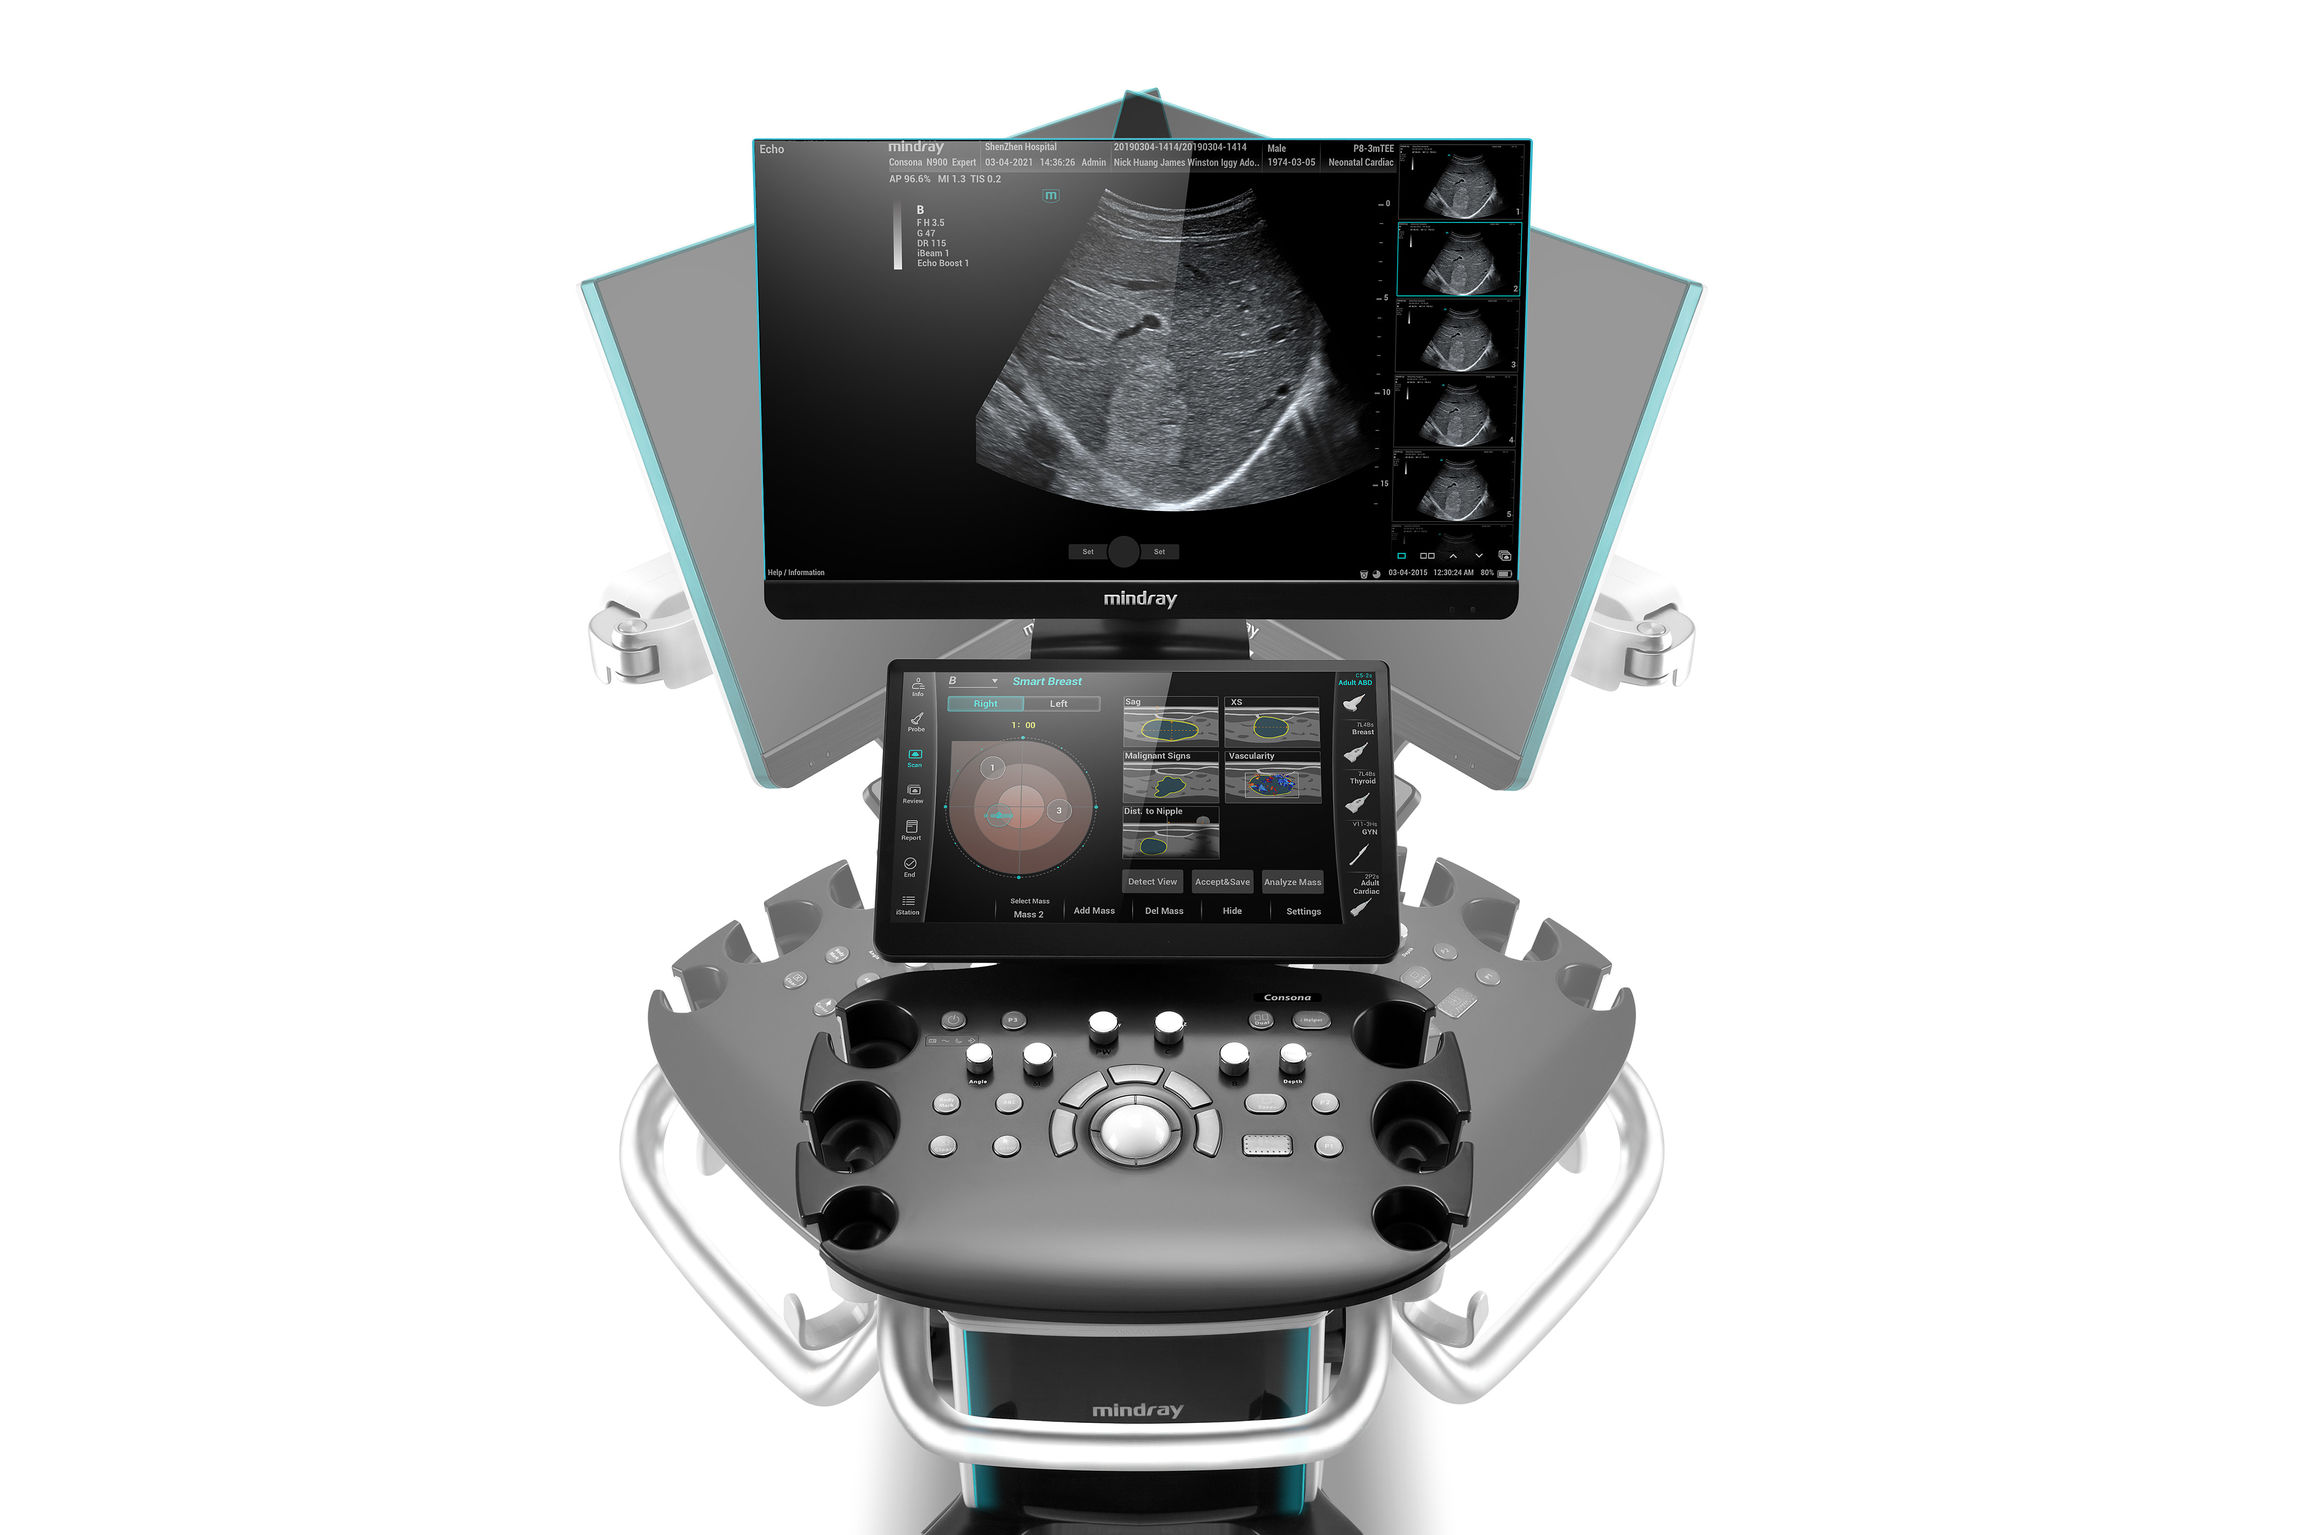

The Mindray Consona N6 Ultrasound System is an advanced and compact ultrasound system designed for a wide range of clinical applications. With its high-quality imaging capabilities, it delivers exceptional resolution and depth penetration for accurate diagnostic evaluations. The Zone sonography platform is very different from conventional beamformer technology. Your advantages are an ultra-fast image build-up and a B-image that is completely focused from the near field to the depths. Focus on the image, the system will do the rest!

- Patented ZST+ technology and HD Scope algorithm provide high image quality.

- Faster investigations with SMART functions such as Smart Bladder, SmartTrack, Glazing Flow, Smart Vue and Smart Calc.

- Entire ultrasound image in focus – no focal points.

Comprehensive Imaging Solutions Powered by ZST+

The ZST+ platform is an extraordinary innovation, representing an ultrasound evolution. Transforming ultrasound metrics from conventional beam-forming to channel data-based processing. It overcomes the traditional trade-off limitation among spatial resolution, temporal resolution and tissue uniformity, delivering exceptional image quality for infinite imaging solutions with non-stop improvements.

Comprehensive Clinical Solutions

Concrete to Resonate

Dedicatedly designed for primary care users, the Consona features new and concrete solutions, that efficiently help you to carry out smooth diagnoses for extensive types of patients.

No matter whether your routine is in hospitals or clinics, or you are honing skills in General Imaging applications, women’s health care or cardiovascular specialties, you will find highly powerful tools available in this series to keep you ahead.